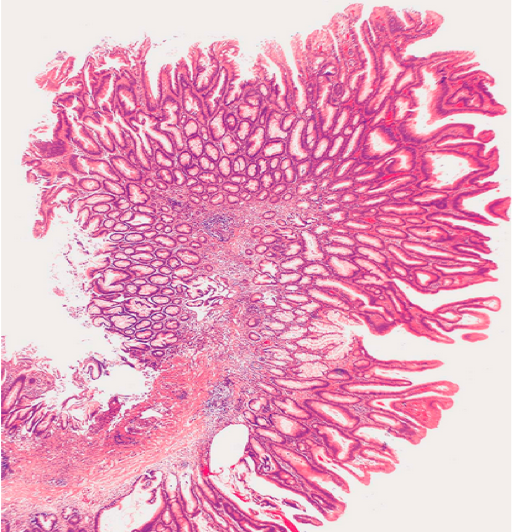

(3)管状腺瘤(绒毛状腺瘤)

呈息肉状,可有蒂,常见于结肠、直肠粘膜管状绒毛状腺瘤:肿瘤性腺上皮形成分化好的小管和绒毛状结构并存,癌变率高。